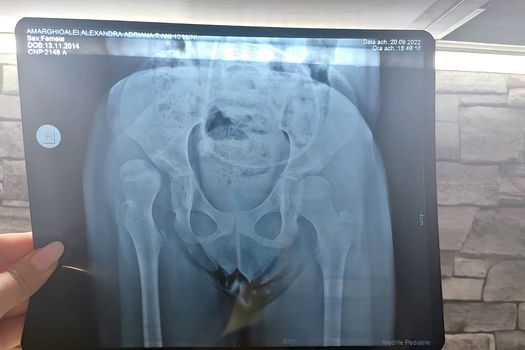

Alexandra este o fetiță de 7 ani care s a născut prematur la 25 de săptămâni. În urma prematurității, Alexandra a suferit mai multe afecțiuni, accident vascular grad 4, epilepsie, poroncefalie, hidrocefalie și o hemipareza pe partea dreapta, meningită bacteriană.

Alexandra are un șunt ventriculoperitoneal care o ajută la drenarea lichidului cefalorahidian. Șuntul este un dispozitiv utilizat pentru a diminua presiunea excesivă asupra creierului.

Pentru ca acest lucru să se întâmple, Alexandra are nevoie de câteva operații pe care doctorul ortoped le-a recomandat urgent, în urma unor investigații amănunțite:

• Repunere sângerândă șold drept;

• Osteotomie de bazin;

• Osteotomie de baricade femur proximul drept;

• Tenotomie de adductori coapsa dreaptă.